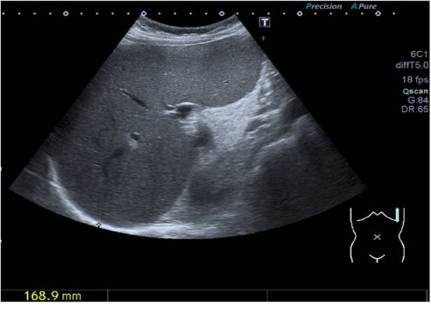

El ejemplo de la foto anterior observamos un bazo medido y su medida abajo a la izquierda de la imagen.

When we have a structure that we want to measure, for example, the size of the Spleen, we will locate the image, then we will freeze it and if we like it, we proceed to make a measurement. For this we will press the button of measures, in the screen it will appear a command in the form of «+» or of «*» or in some similar way, we will take with the trackaball that command until the beginning of the structure that we want to measure, we will press the button «SET» or identical function button even if it does not have this name (trademarks) that is usually next to trackball, setting that first command and move another sign like the one we used and that appears when you press «SET» to the point end of the structure to be measured, again, of course, with the trackball. A measure will appear on the screen, corresponding to the size of the study structure. Easy. The example in the previous photo shows a measured spleen and its measurement at the bottom left of the image. We can repeat this as many times as we wish by pressing the measurement button again.